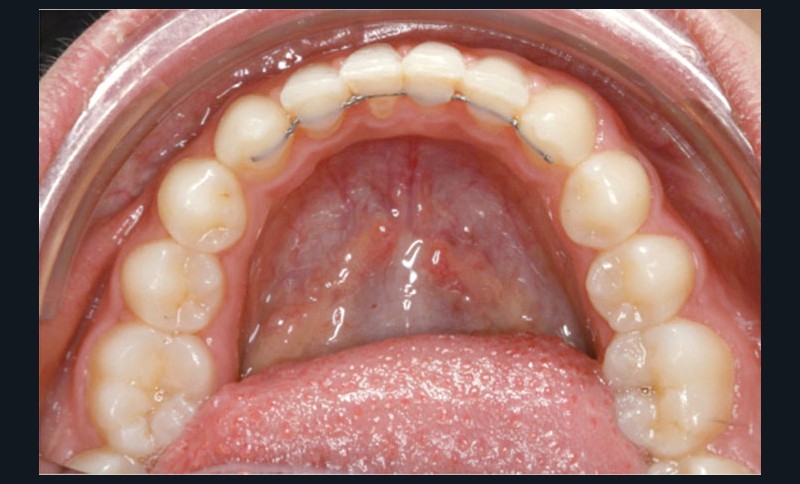

La décision thérapeutique s’est orientée dès cette consultation vers la fermeture des espaces d’agénésie et l’extraction de la 52 a été réalisée à ce stade pour respecter la symétrie antérieure et favoriser l’évolution symétrique des deux canines en position d’incisives latérales.

Les vues endo-buccales après extraction de 52 montrent des relations occlusales de classe II, un léger encombrement incisif mandibulaire et une tendance à la fermeture spontanée des espaces des incisives latérales confirmant le choix thérapeutique d’une fermeture d’espace (fig. 2).